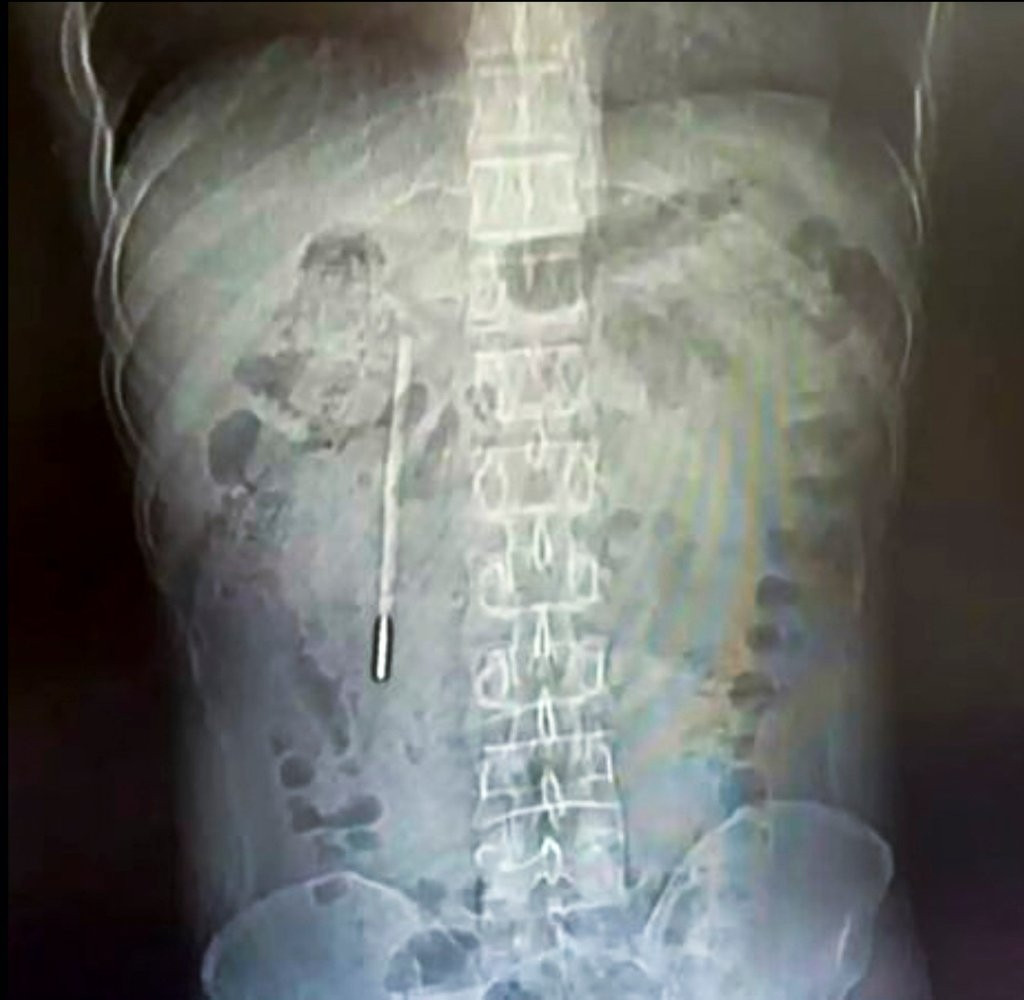

Theo kết quả từ các biện pháp chẩn đoán hình ảnh và chụp chiếu, các bác sĩ chuyên khoa đã phát hiện một dị vật nằm sâu bên trong tá tràng của bệnh nhân. Căn cứ vào hình dáng và đặc điểm trên phim chụp, đội ngũ y tế đã đặt ra nghi ngờ rất lớn rằng vật thể lạ này chính là một chiếc nhiệt kế thủy ngân.

Tình trạng lúc bấy giờ được đánh giá là vô cùng nguy hiểm. Phần đầu nhọn của chiếc nhiệt kế đang trong trạng thái ép trực tiếp vào lớp thành ruột của bệnh nhân. Vị trí và tư thế này đặt ra một nguy cơ cực kỳ cao về việc gây thủng ruột và dẫn đến tình trạng chảy máu trong nghiêm trọng, đe dọa trực tiếp đến tính mạng của người bệnh nếu không được can thiệp kịp thời.

Nhận thức được mức độ nghiêm trọng của ca bệnh, các bác sĩ phẫu thuật đã nhanh chóng triển khai một ca mổ khẩn cấp. Quá trình can thiệp y tế để lấy dị vật ra khỏi cơ thể chỉ diễn ra trong vòng hai mươi phút ngắn ngủi nhưng lại đòi hỏi sự tập trung cao độ.

Đây được xem là một ca phẫu thuật cực kỳ tinh tế và phức tạp do chiếc nhiệt kế đã bị lưu lại bên trong cơ thể người bệnh trong một thời gian quá dài. Thêm vào đó, vị trí của nó nằm rất gần với các ống mật của Vương, tạo ra một rủi ro đáng kể về việc làm tổn thương lớp thành ruột xung quanh trong quá trình di chuyển dị vật.

Rất may mắn, thiết bị được lấy ra vẫn còn giữ được hình dạng nguyên vẹn ban đầu, mặc dù các vạch đo nhiệt độ in trên thân nhiệt kế đã bị mờ nhạt đi theo thời gian do tác động của môi trường dịch vị.